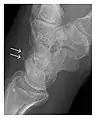

Triquetral fracture usually occurs on the dorsal aspect by impingement from the ulnar styloid or avulsion of strong ligamentous attachment. The dorsal avulsion fracture or "chip fracture" appears as a small bony fragment on the dorsal aspect of the triquetrum and is best detected on the lateral view(Figure 4). When radiography is negative in patients with high suspicion of a fracture, both MRI and MDCT will be of value. However, it has been shown that MRI is superior for detecting trabecular fractures in carpal bones.

- a

- b

Figure 4: Dorsal triquetral fracture of the left wrist in a 30-year-old man after a trauma. (a) Anteroposterior radiograph shows a normal appearance. (b) Lateral radiograph of the same wrist demonstrates a chip fracture off the dorsal aspect of the triquetrum (arrow).[1]